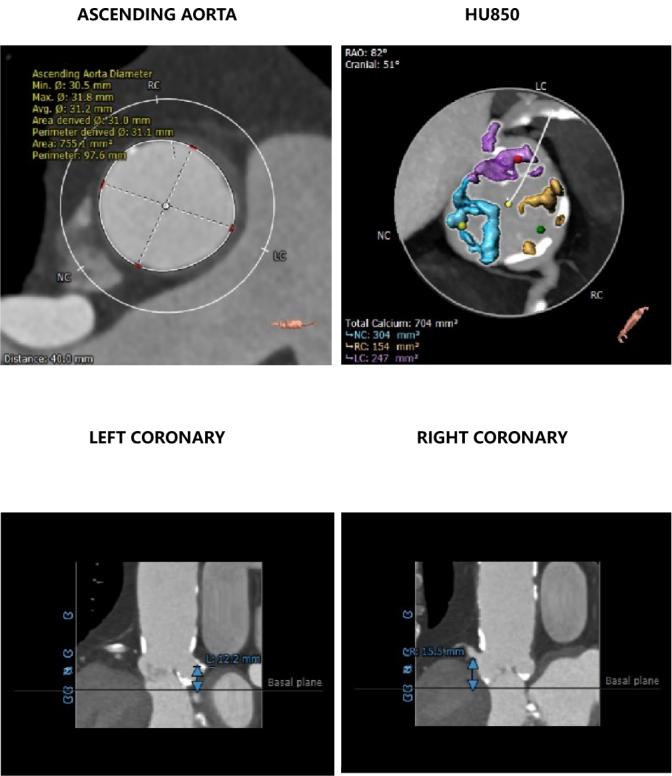

CT数据显示该患者为三叶三窦式主动脉瓣。

主动脉瓣瓣环周长70.8mm,平均周长径 22.6mm,SOV:31.9mm*28.0mm*29.0mm,瓣叶增厚,瓣上见明显钙化,瓣环水平夹角48°,左冠高度12.2mm,右冠高度15.5mm,HU850钙化积分704mm³。

钙化评估及主动脉弓影像:

HU623钙化积分1337mm³,主动脉弓见大量钙化。